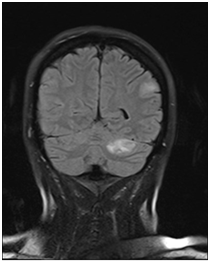

CT& MRI of the brain revealed multiple rounded enhancing masses scattered through the brain and are likely to be cerebral metastases. One lesion in left cerebellar lesion showed a little high signal in the CT head & brain MRI, this feature is a characteristic for haemorrhagic phenomena or presence of melanin in melanoma metastasis (Figure 3).

Figure 3 Head MRI: Left cerebellar lesion with a high signal on T1 sequence.